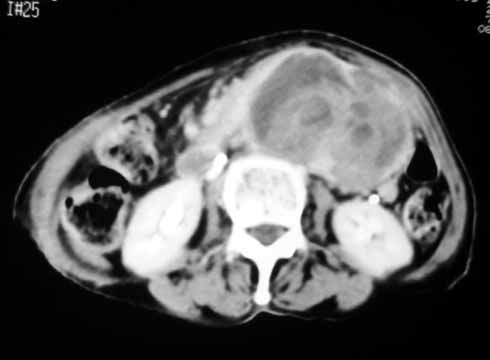

以下是引用天南地北在2007-4-30 17:42:00的发言:[br]增强扫描显示腹主动脉给包绕、推移。肿块不规则强化,[br]修正我在平扫的诊断[br]支持考虑:间叶源性肿瘤可能性大

以下是引用余辉在2007-4-30 18:01:00的发言:[br]病灶前方的条状增强影是什么?若是胰腺,位置似乎有点低,若是十二指肠,似乎又不诫该是那样强化,姑且将其看作胰腺吧,那么考虑来源于胰腺粘液囊腺瘤可能性大,其次考虑来源于肠系膜或者后腹膜的肿瘤如平滑肌肉瘤,异位嗜铬细胞瘤及淋巴瘤等。

以下是引用zyx168在2007-4-30 23:24:00的发言:[br]考虑:间叶源性肿瘤可能性大